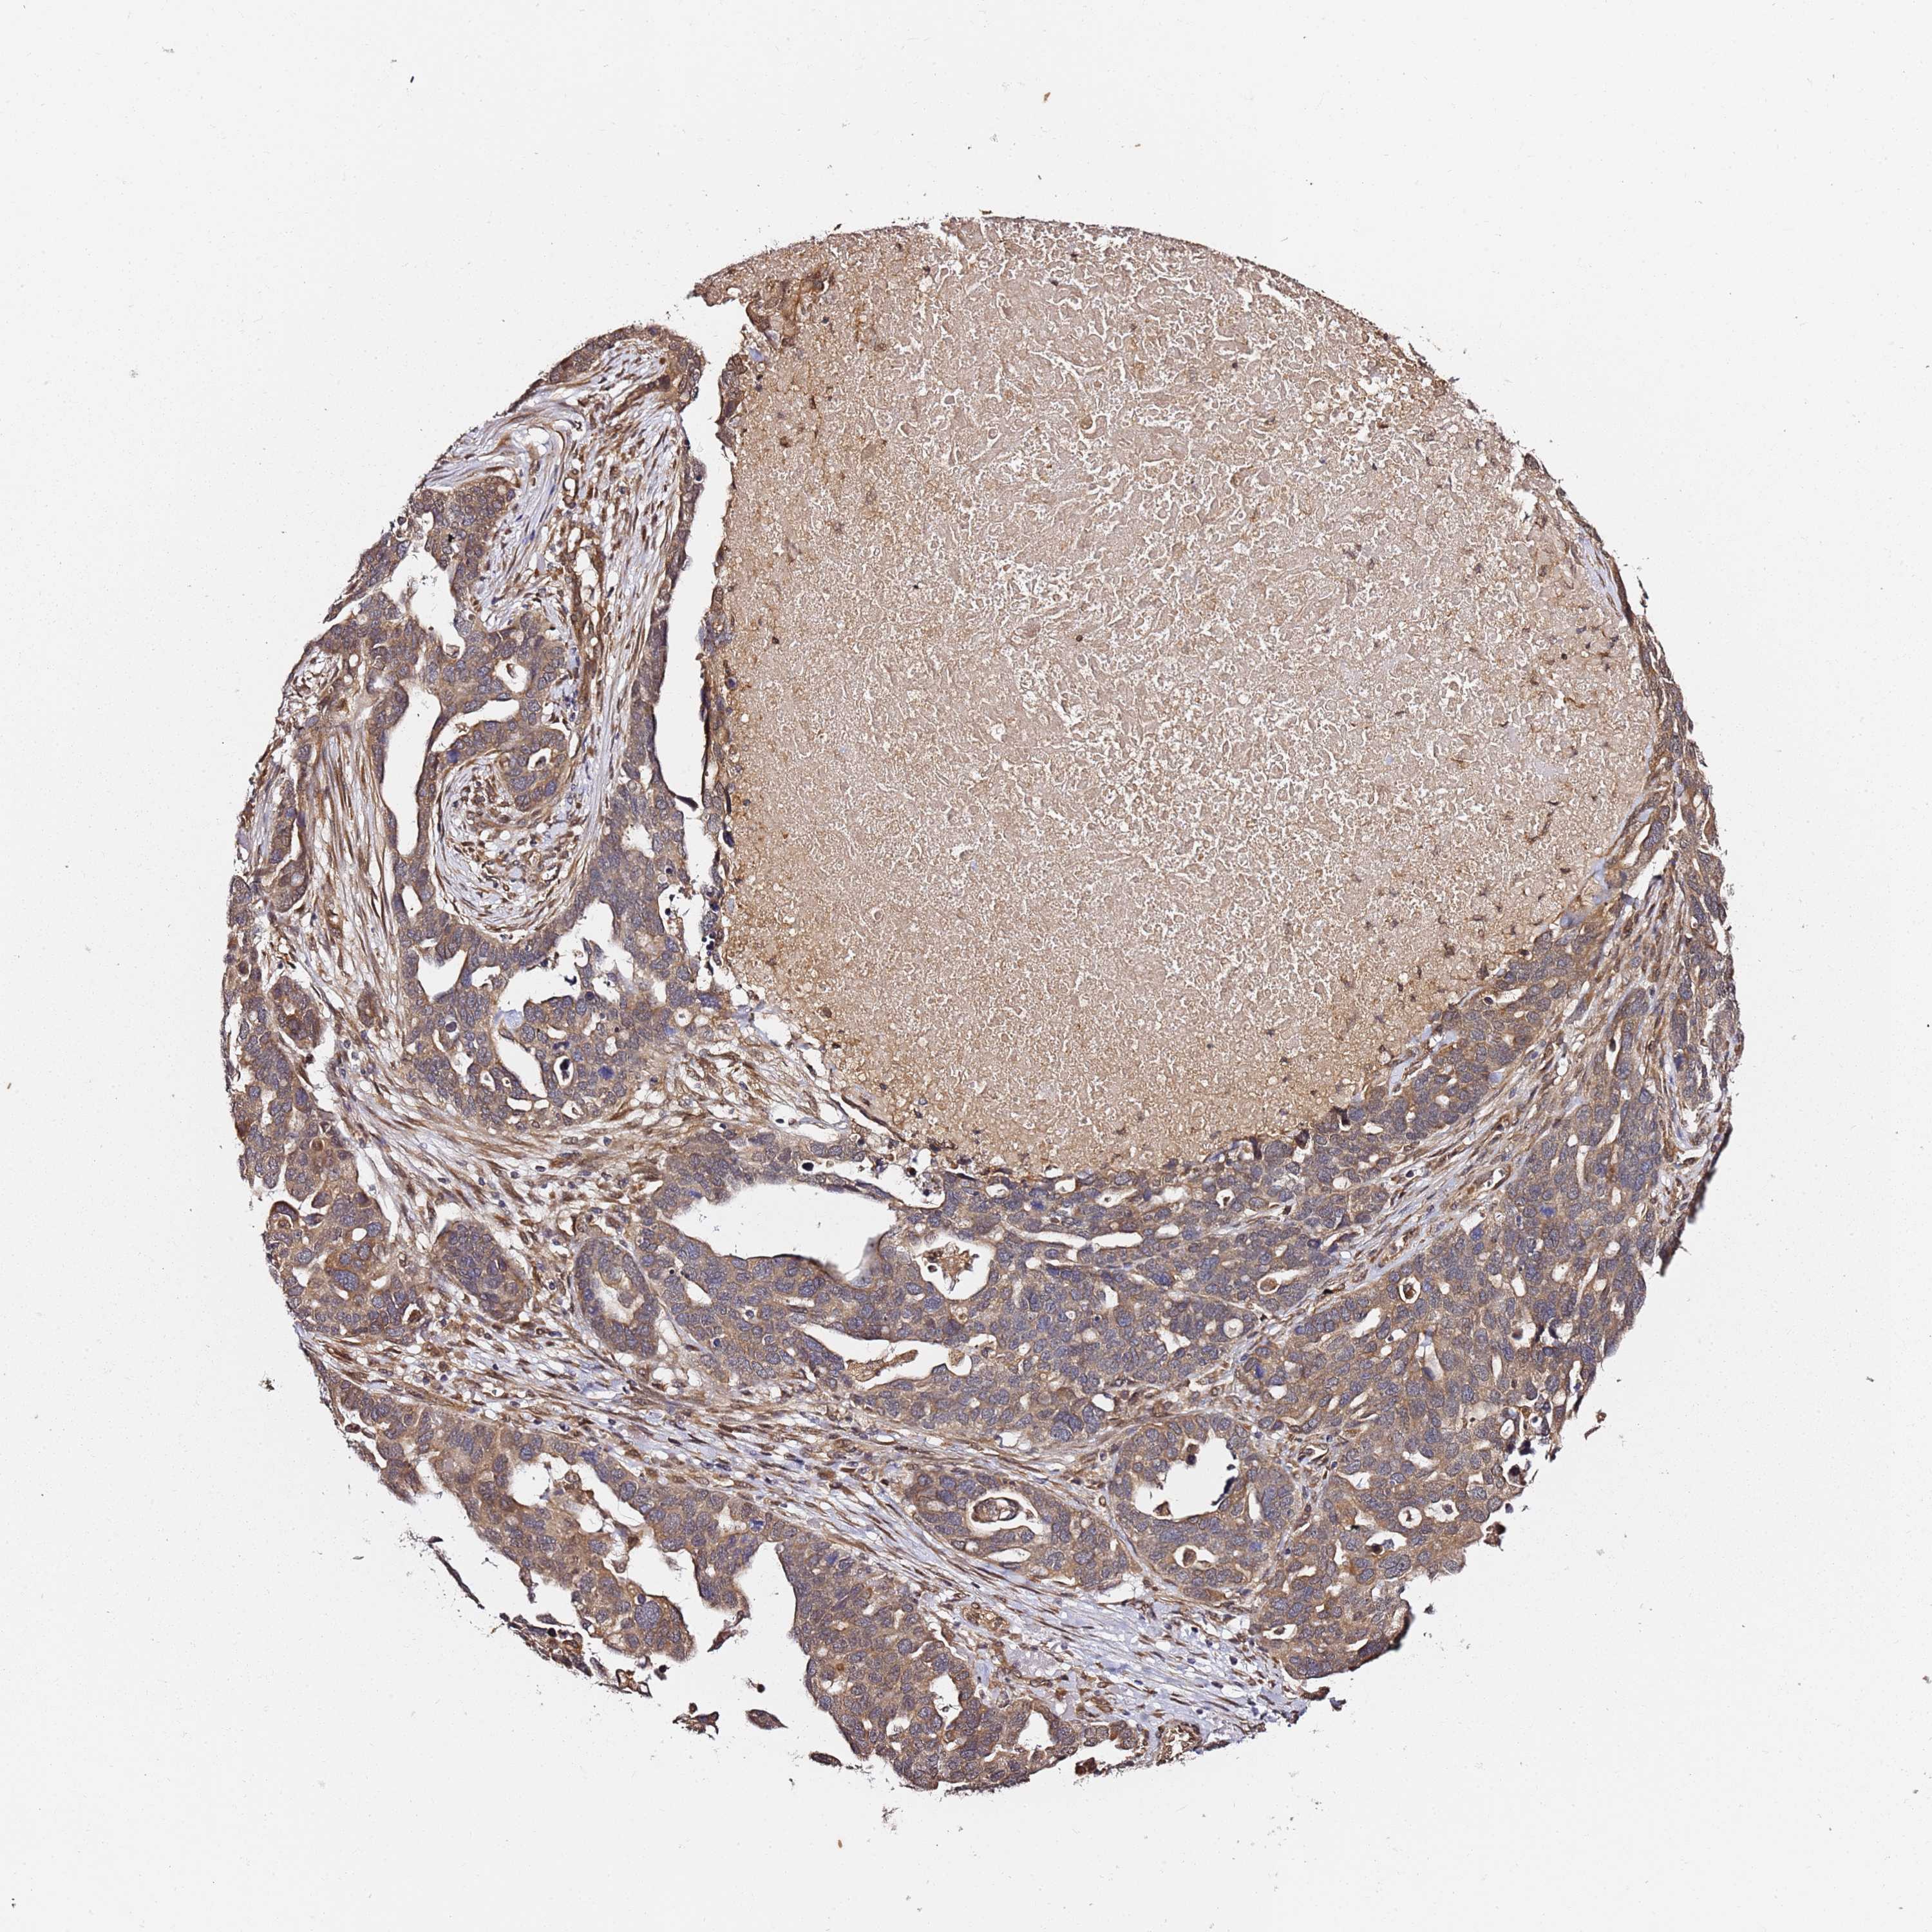

OVARIAN CANCER - Protein expressioni

A mouse-over function shows sample information and annotation data. Click on an image to view it in a full screen mode. Samples can be filtered based on level of antibody staining by selecting one or several of the following categories: high, medium, low and not detected. The assay and annotation is described here.

Note that samples used for immunohistochemistry by the Human Protein Atlas do not correspond to samples in the TCGA dataset.

Antibody stainingi

Antibody staining in the annotated cell types in the current human tissue is reported as not detected, low, medium, or high, based on conventional immunohistochemistry profiling in selected tissues. This score is based on the combination of the staining intensity and fraction of stained cells.

Each image is clickable and will lead to virtual microscopy that enables deeper exploration of all samples and also displays staining intensity scores, fraction scores and subcellular localization as well as patient and tissue information for each sample.

Antibody HPA044342

Staining

High

Medium

Low

Not detected

Intensity

Strong

Moderate

Weak

Negative

Quantity

>75%

75%-25%

<25%

None

Location

Nuclear

Cytoplasmic/membranous

Cytoplasmic/membranous,nuclear

Cystadenocarcinoma, serous, NOS

Carcinoma, endometroid

Cystadenocarcinoma, mucinous, NOS

Carcinoma, NOS